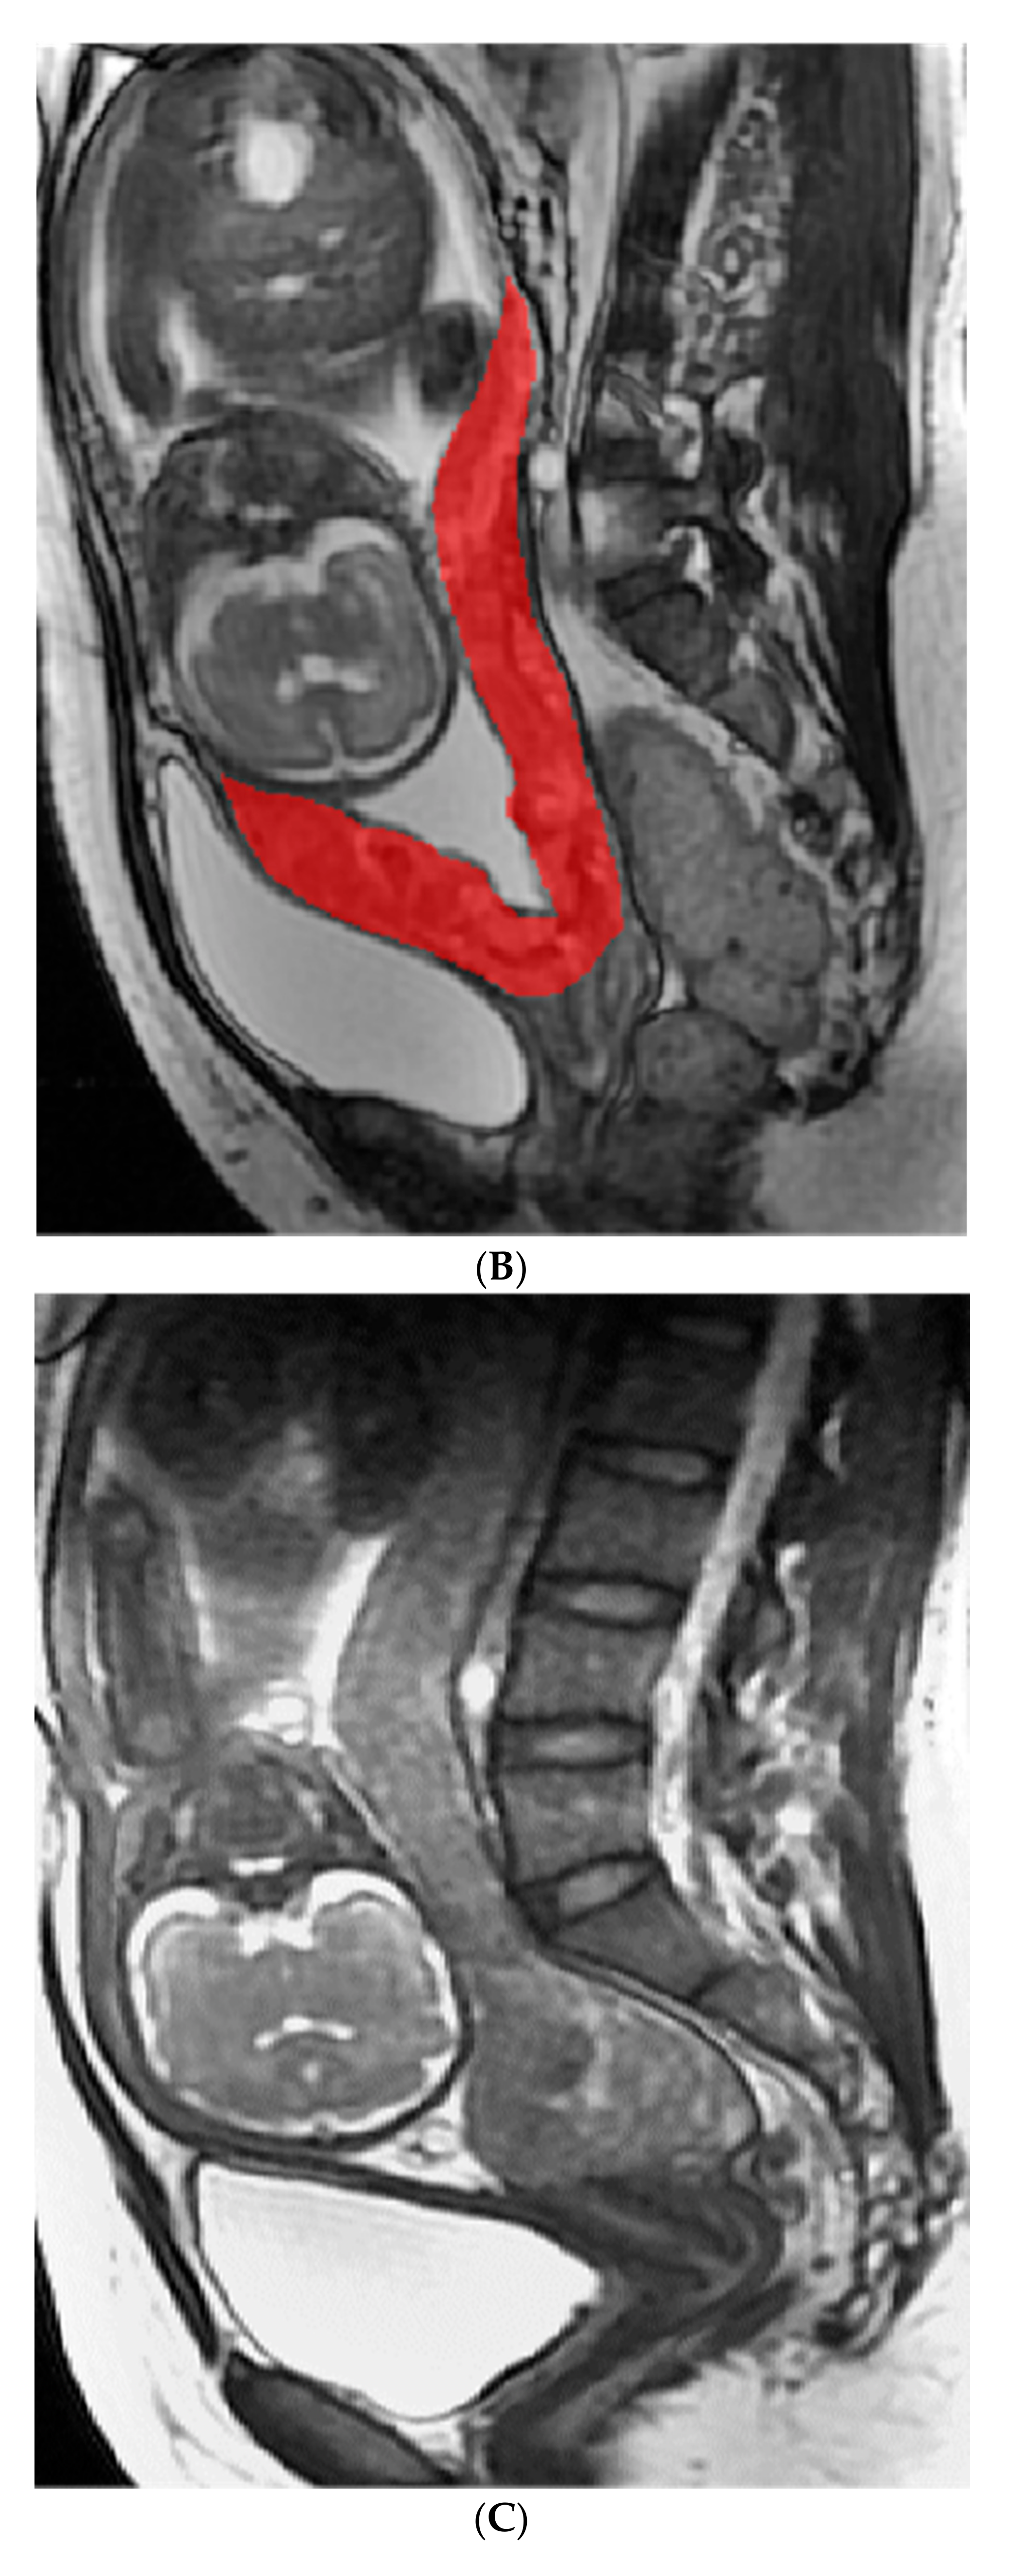

4.4.1. Image Analysis and Segment